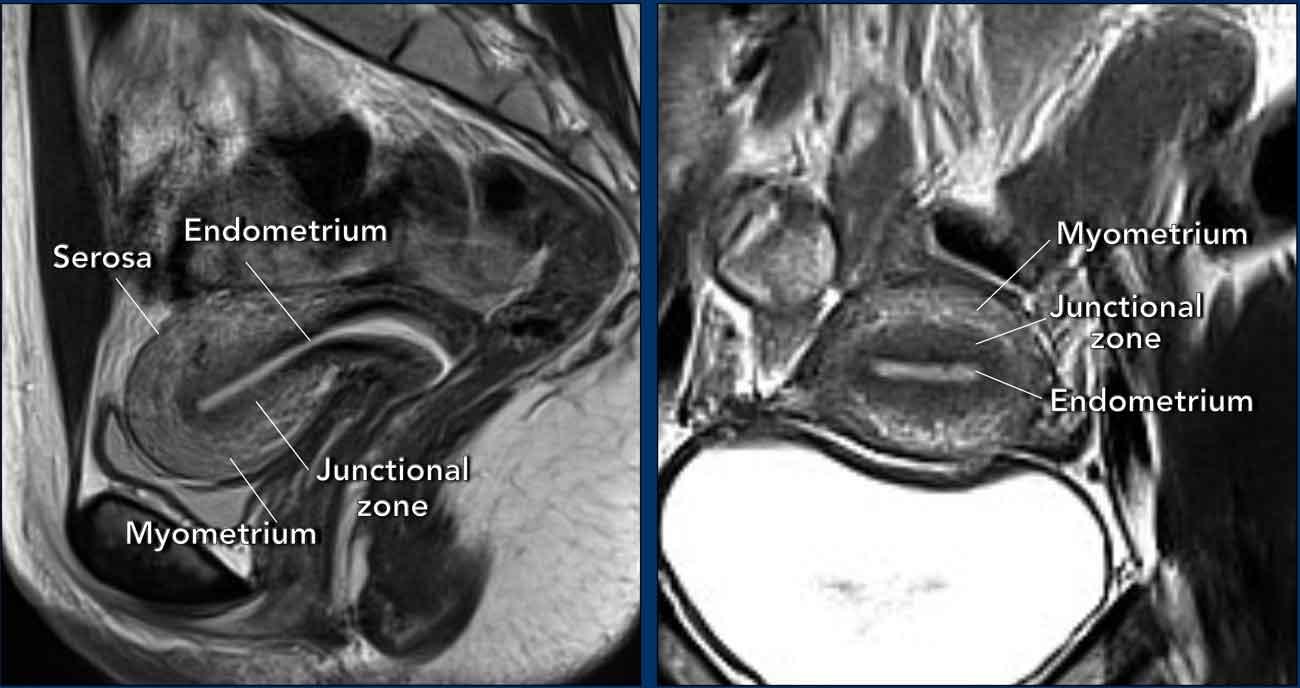

Giải phẫu tử cung được thể hiện rõ nhất trên chuỗi xung T2W.

Trong độ tuổi sinh sản, có thể nhận diện ba lớp vùng riêng biệt: lớp nội mạc tử cung (tăng tín hiệu), vùng tiếp hợp (giảm tín hiệu) và lớp cơ tử cung (tín hiệu tương đối cao).

Bề mặt ngoài của lớp cơ tử cung, hay còn gọi là thanh mạc, có thể được nhận diện dưới dạng một đường giảm tín hiệu mảnh.